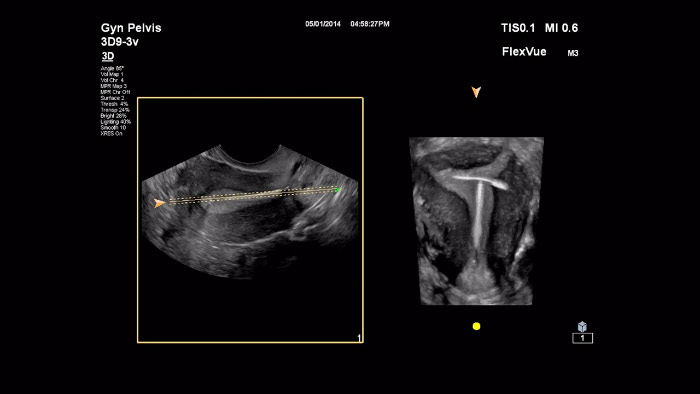

Dans cette vidéo, le Dr Michael Ruma présente FlexVue, l’outil d’évaluation 3D avancé de Philips. FlexVue permet une visualisation facile des vues anatomiques techniquement difficiles à partir de volumes 3D, essentielles au diagnostic des pathologies obstétricales/gynécologiques.